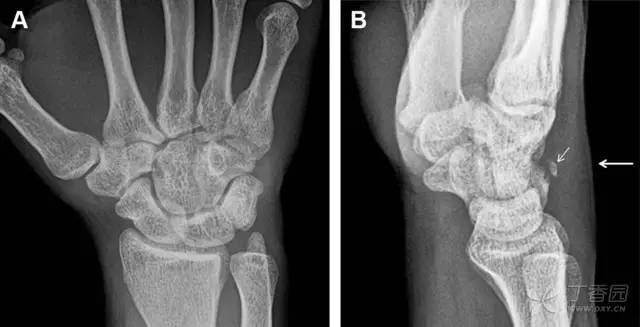

36 腕关节不稳定与脆弱区

月骨周围脱位和月骨周围骨折脱位常发生于摔倒后手掌撑地,由过伸、轴向*力暴**所致。所谓的「脆弱区」包括桡骨茎突、大多角骨、舟状骨、头状骨近端、钩状骨近端、三角骨的月骨缘、尺骨茎突。

图 7 经舟状骨骨折月骨周围脱位(腕关节前后位、斜位、侧位)。(A,B)前后位、斜位示月骨腰部骨折(黑箭头),第 1、2 腕弧中断,舟状骨近极(*)仍在原位,而远极(虚线)背侧脱位